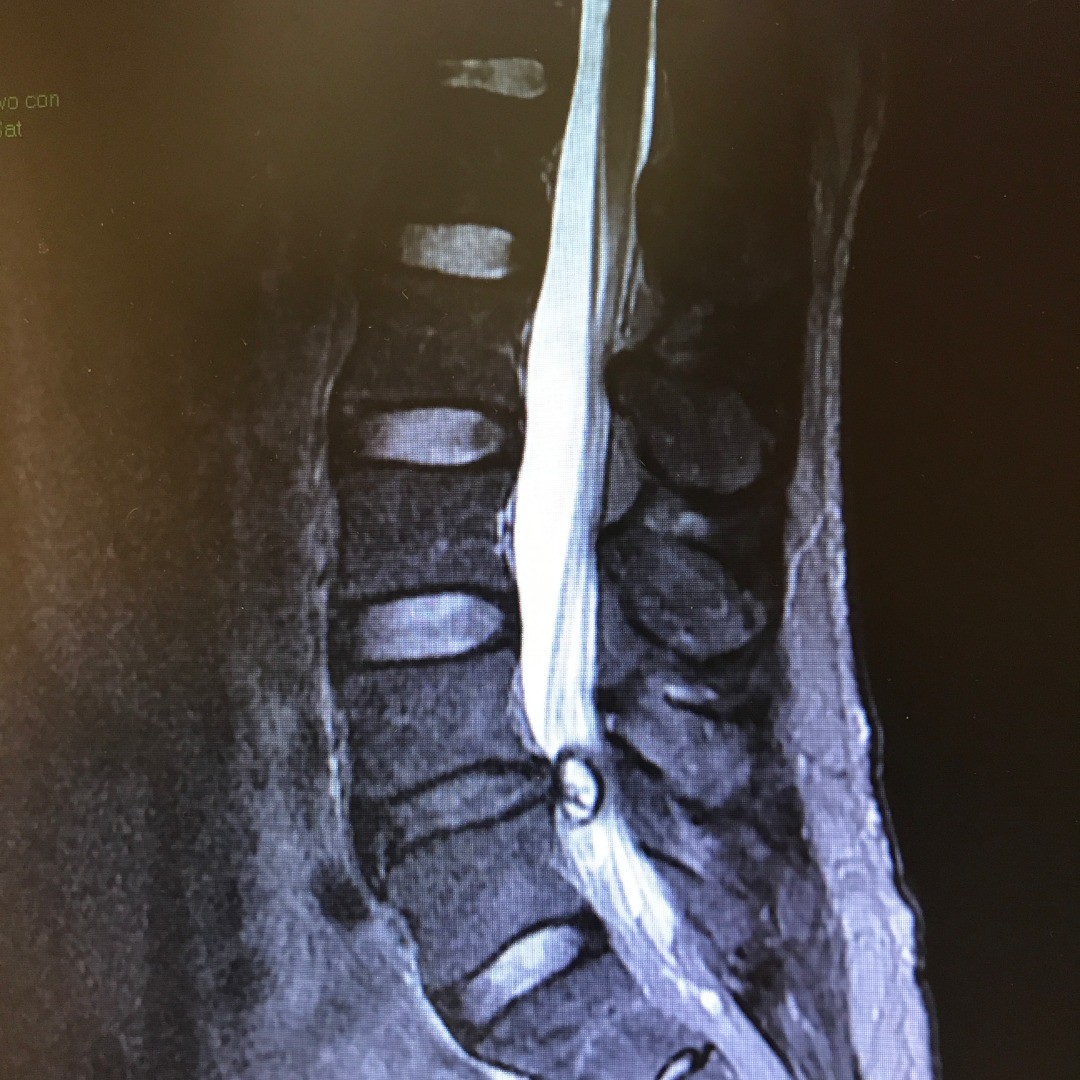

Lumbar Spinous Process Plating is a minimally invasive technique in which a metal device, such as the CD HORIZON® SPIRE™ implant, is used to stabilize the spine. This is done by implanting it onto the patient’s spine through an incision in the lower back. This technique is typically combined with additional implants such as pedicle screw fixation or interbody cage devices in order to increase the chances of achieving optimal rigid spinal fixation and fusion.

Lumbar Spinous Process Plating is used in order to give you relief from back problems. Such back issues can include conditions like degenerative arthritis, spondylolisthesis, and spinal stenosis. After the failure of non-surgical techniques, surgical intervention might be necessary.